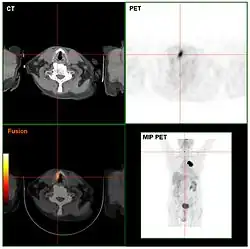

Computed tomography (CT) and positron emission tomography (PET) scans are similar to MRI, but rely on different imaging techniques (X-rays and ionizing radiation, respectively). A variation of CT known as contrast CT also requires the subject to take in a contrast medium called a radiocontrast (typically by oral consumption, enema, or injection). Positive radiocontrast agents such as barium sulfate increase the body's X-ray attenuation, causing the tissue containing them to appear whiter in the X-ray image. Meanwhile, negative agents such as carbon dioxide gas allow X-rays to pass through them easily, causing the tissues containing them to appear darker.[49]

Like magnetic resonance imaging, CT scans use numerous methods to display and measure data, including sequential CT (where the CT table steps from location to location), spiral CT (where the entire X-ray tube is spun around the subject), and electron beam tomography (where only the electron paths are spun using deflection coils). PET scanners don’t have quite as much hardware variation and instead use different radiotracers depending on what the imaging target is. Note that radiotracers are distinct from radiocontrasts; the former relies on radioactive decay to trace its path while the latter is absorbed into specific tissue and affects that tissue's X-ray attenuation. Because these methods are not mutually exclusive, PET and CT can be performed simultaneously using PET-CT scanners, which are used for the majority of modern PET scans.[50]

Either or both of these methods can be used in conjunction with maximum intensity projection (MIP) to convert the scan data into a 3D image. This can be difficult to accomplish due to artifacts created by respiration and bloodflow, which can appear as abnormalities to an untrained eye; however, it's possible to distinguish these artifacts from real disease so long as careful attention is paid to them.[51] When done well, CT and PET scans taken with MIP are excellent for identifying small abnormal tissue growths, especially in the lungs. Scans taken with MIP for this purpose tend to have higher significance than averaged images created with traditional CT.[52]